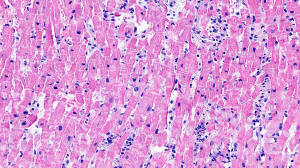

Figure A: H&E staining, 20x

Histology: H&E staining ( Figures A, B, C) show predominant interstitial edema and lymphocytic infiltration with myocyte damage and necrosis (Figures A, B, C). Trichrome staining (Figure D) highlights the myocyte necrosis.